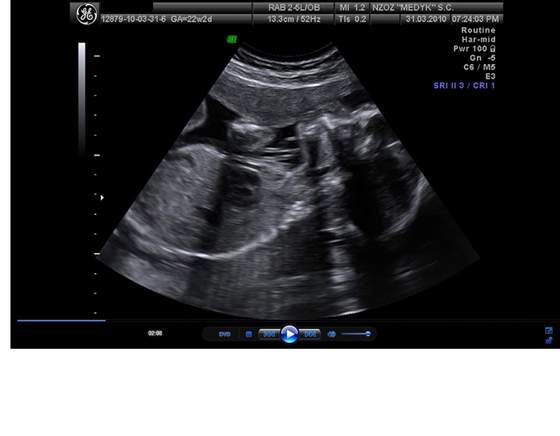

Pola juz po usg połowkowym. Jest zdrowiutka ma już 25 cm razem z nożkami i waży koło 350g. I jets strasznym wiertkiem. Załączam zdjątka

3.Pola